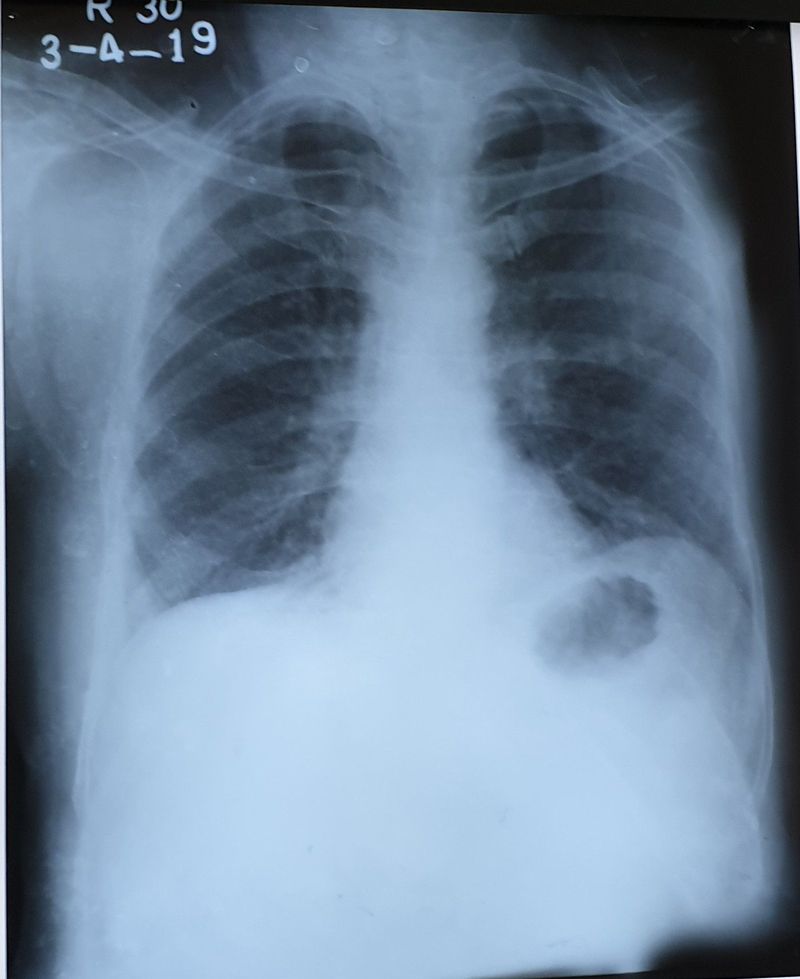

What's your diagnose ?

Spleenomegaly?🤔

Cancer of stomach? Or Hernia

Rib Fracture??

Cancer?!

Left diaphragmatic hernia